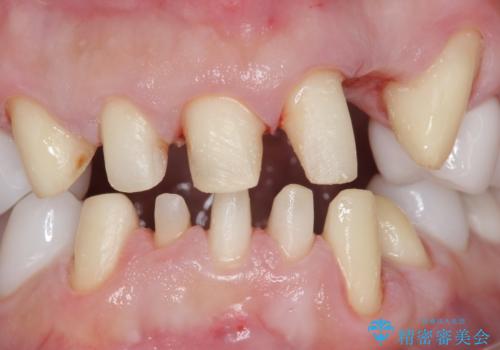

- 歯並びをきれいにしたい、歯を真っ白にしたいとのご希望により来院されました。

矯正治療とホワイトニングを提案しましたが希望されず、「接客関係の仕事で矯正治療は考えられない、短期間で治療を終わらせたい、ホワイトニングでは難しい位の人工的な白さにしたい」とのご要望により、治療前にワックスアップ模型を作製し何度もコンサルテーションを重ね、治療方針を決定しました。

歯頚ラインが変えられないことや天然歯を削るリスクをご理解頂いた上で、オールセラミッククラウンによる補綴治療を行いました。(見えない奥歯のみ天然歯のままとしました)

下の前歯1本だけ歯軸を変えるために神経をとり根管治療を行っております。

それ以外の歯は神経をとらずに済むよう、慎重かつ丁寧に歯の形態を整えました。

治療前に埋伏している親知らずの抜歯をおすすめしましたが、ご希望されませんでした。